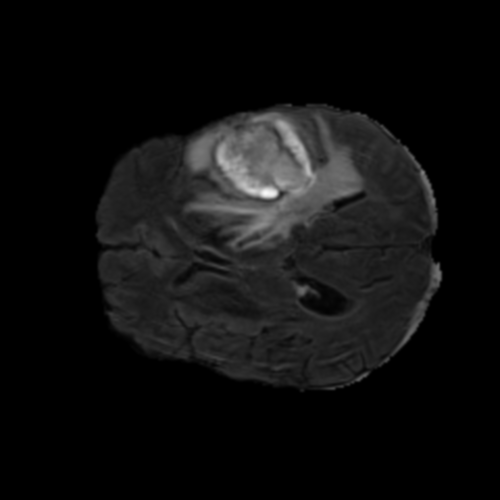

Ejemplos de Modalidades MRI

Visualización de las 4 modalidades de resonancia magnética y las segmentaciones de zonas tumorales utilizadas para entrenar el modelo

Glioma de Alto Grado (HGG)

FLAIR HGG

FLAIR

T1ce HGG

T1ce

T2 HGG

T2

T1 HGG

T1

Núcleo HGG

Núcleo

Edema HGG

Edema

Realce HGG

Realce

Tumor Completo HGG

Tumor Completo

Núcleo Edema Realce